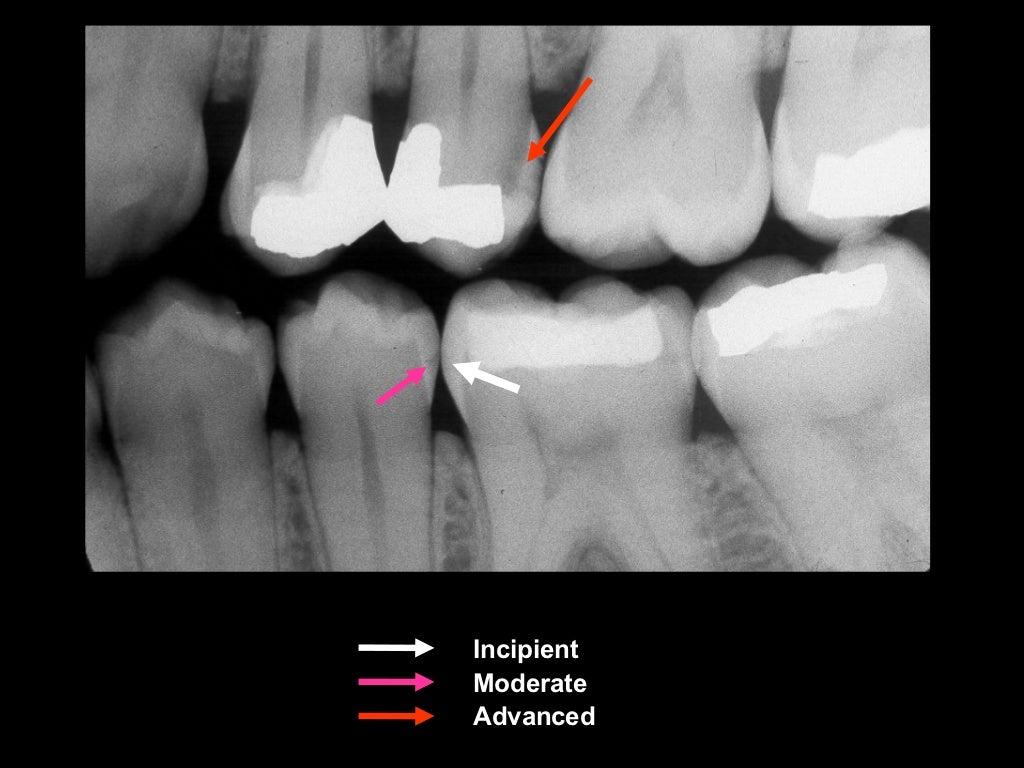

Occlusal Caries X Ray . Dental caries recurs if not completely excavated before restoration, and lesions appear as radiolucency adjacent to or beneath the restoration. One of the most frequent reasons for using dental radiography is to aid in caries detection. Small occlusal lesions, buccal and lingual pit cavities, are better studied clinically, as radiography plays a small role in the detection of these lesions. The carious process results in. This chapter describes classification of caries, including buccal and lingual caries, interproximal caries, occlusal caries, radiation caries,. Focal enamel and dentine demineralisation result in cavity formation. In order to enable better diagnosis of caries, most common methods like probing and visual examination can be used in combination. Radiographs are often essential for the early detection of interproximal caries. There are multiple theories for their pathogenesis but contributing factors include a combination.

One of the most frequent reasons for using dental radiography is to aid in caries detection. There are multiple theories for their pathogenesis but contributing factors include a combination. The carious process results in. Small occlusal lesions, buccal and lingual pit cavities, are better studied clinically, as radiography plays a small role in the detection of these lesions. Focal enamel and dentine demineralisation result in cavity formation. Radiographs are often essential for the early detection of interproximal caries. Dental caries recurs if not completely excavated before restoration, and lesions appear as radiolucency adjacent to or beneath the restoration. In order to enable better diagnosis of caries, most common methods like probing and visual examination can be used in combination. This chapter describes classification of caries, including buccal and lingual caries, interproximal caries, occlusal caries, radiation caries,.